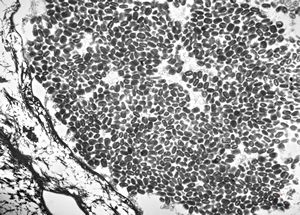

M, 62y. | mitosis … angiomatous tumor, v.s. Kaposi sarcoma

M, 62y. | angiomatous tumor, v.s. Kaposi sarcoma